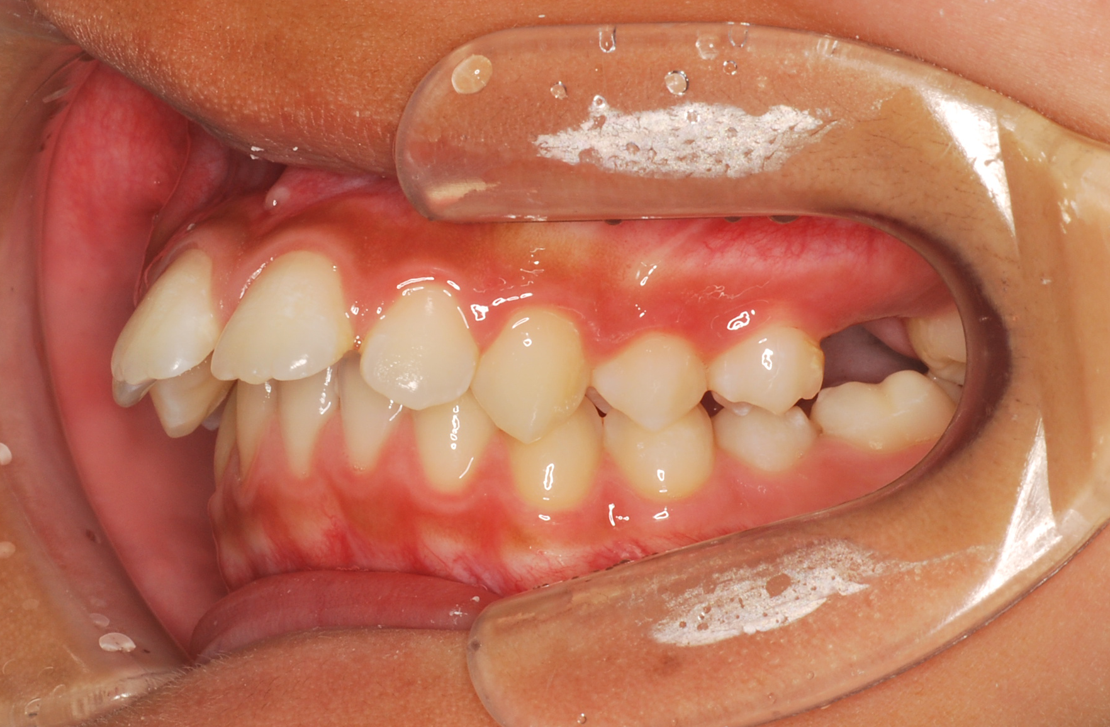

• 治療前

• 治療後

主訴:歯並びのガタガタ

診断:叢生

治療内容:舌側矯正治療

年齢:27歳

治療に用いた装置:マルチブラケット装置(舌側)

抜歯or非抜歯:抜歯(上下顎両側小臼歯)

期間:30ヶ月

回数:30回

費用:1,639,000円(税込)

リスク・副作用:虫歯、歯肉炎、歯肉退縮、歯根吸収、後戻りなど